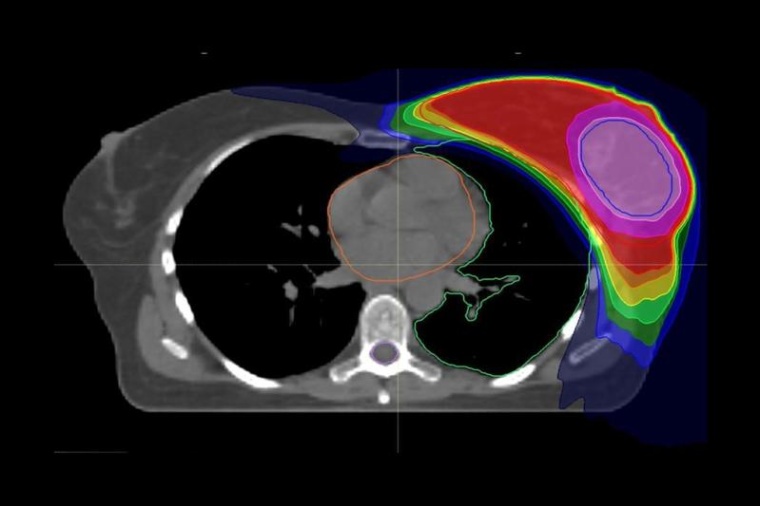

Die aktuellen Leitlinien der Amerikanischen Gesellschaft für Radioonkologie (ASTRO) zur Strahlentherapie bei Brustkrebs empfehlen bislang noch die anschließende Boost-Bestrahlung. „Das liegt daran, dass es bisher noch keine belastbaren Daten zur Bewertung des integrierten Boosts gab“, so Prof. Dr. Dr. Jürgen Debus, Ärztlicher Direktor der Radiologischen Universitätsklinik und Letztautor der Studie. „Unsere Ergebnisse sind ein erster wichtiger Schritt zur evidenzbasierten Aktualisierung der Leitlinien.“ Insbesondere moderne Bestrahlungstechniken wie die Intensitätsmodulierte Radiotherapie (IMRT), bei der Risikoorgane bestmöglich geschont werden können, haben der neuen Entwicklung den Weg geebnet. Inwieweit sich die Ergebnisse auf die seit rund drei Jahren zunehmend angewandte, verkürzte Radiotherapie der Brust übertragen lassen, ist Gegenstand aktueller Studien.